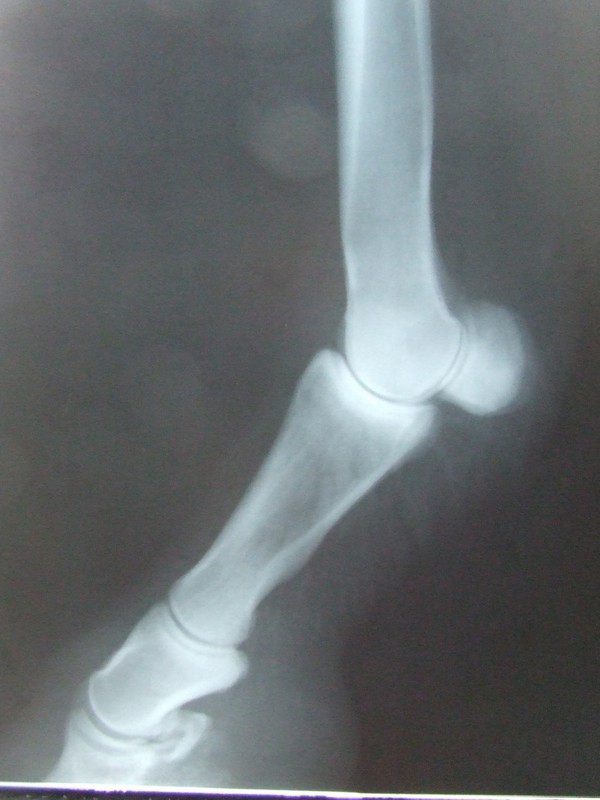

RTG

pravá přední

Pravá přední 19.3.20009